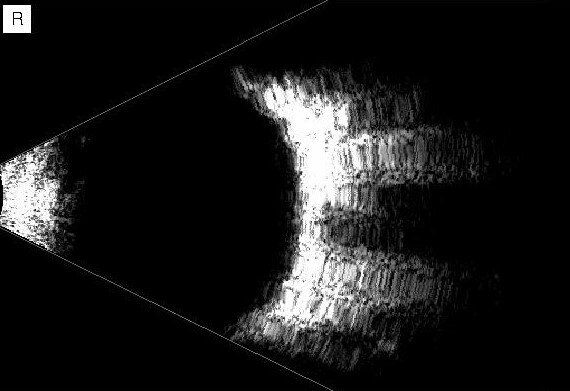

Hier sehen Sie eine Auswahl unserer innovativen Diagnosegeräte, die präzise Analysen ermöglichen und eine frühzeitige Erkennung von Augenerkrankungen unterstützen. Klicken Sie auf „Weiteres“, um Informationen zu den einzelnen Geräten zu erhalten.